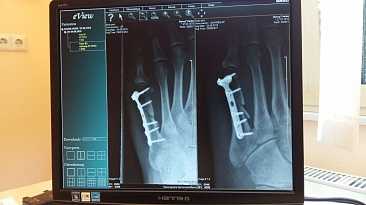

Чем выше контрастность, тем значительнее различие оптических плотностей фона и объекта. Так, на высококонтрастных снимках конечностей светлое, почти белое изображение костей резко вырисовывается на совершенно черном фоне, соответствующем мягким тканям.

Жесткое излучение позволяет получить на рентгенограмме большее число деталей во всей глубине исследуемого объекта. На рентгеновском снимке, произведенном при повышенной жесткости излучения, хорошо видны в деталях как костная, так и мягкая ткани.

Из-за того, что ткани и отдельные органы различаются по плотности и химическому составу, они в разной степени пропускают излучение, что создаёт условия для появления контрастности получающегося изображения и позволяет с достаточной точностью различать отдельные структуры, органы, ткани и их строение.

Широко применяемый метод диагностики позволяющий изучать строение органов в норме и в условиях патологии, в том числе для выявления скрытой патологии. Позволяет диагностировать болезнь, уточнить её стадию, определить место расположения и степень найденных изменений, их протяжённость. Наилучшие результаты получаются при исследовании костной системы и лёгких.